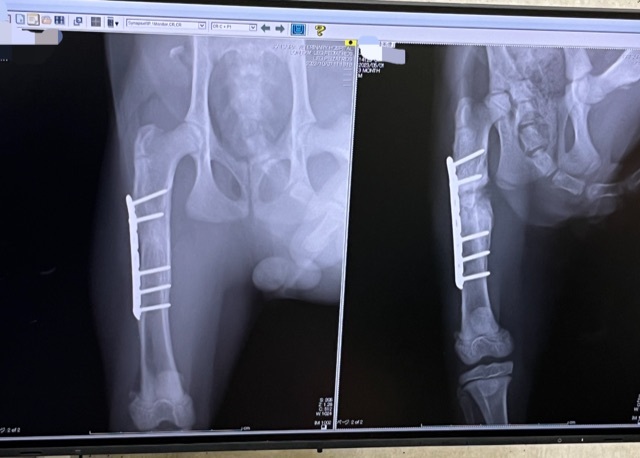

術後の検診

本日約2ヶ月ぶりの検診日でした。

骨の状態も良好でした!

レントゲン写真は左が今日撮影したものです。